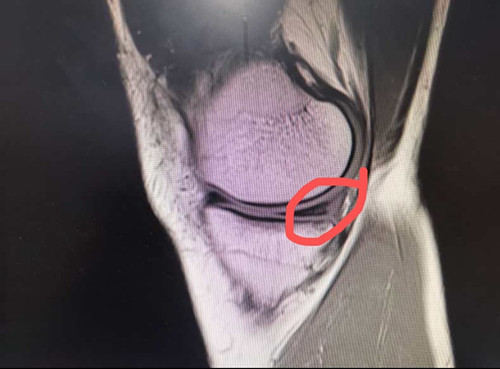

2年前的一场足球友谊赛,对热爱运动的人民警察黄先生来说,是个痛苦的记忆。在那场球赛中他一个高速转身动作,右膝关节扭了一下。紧接着,他感觉一股剧痛从右膝关节传来,整个膝关节无法动弹。送往医院在核磁共振检查后,他的伤情被诊断为:1、右膝前交叉韧带不全断裂2、右膝内外侧半月板后角II度损伤。

这一次,他在熟人介绍下来广西龙潭医院骨外科就诊。接诊的是卢一开主治医师,结合黄先生的病史和体征,对照核磁共振影像学检查,卢医师诊断黄先生右膝关节的损伤符合前交叉韧带完全断裂合并半月板损伤、右膝关节失稳的临床表现。